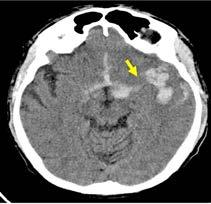

El día 18/2/2022 el paciente refiere dolor torácico. Se realiza un electrocardiograma, que muestra elevación del segmento ST en las derivaciones anteriores en relación con un infarto agudo de miocardio (IAM) anterior. Se activa código infarto y se realiza una coronariografía emergente, que muestra una oclusión de perfil embólico en la arteria descendente anterior media (Figura 1, flecha amarilla). Se trata con trombectomía aspirativa con buen resultado angiográfico final con flujo TIMI 3. Se inicia tratamiento con perfusión de heparina sódica. El día 19/2 el paciente comienza con cefalea muy intensa y afasia, por lo que se activa nuevamente código ictus y se realiza un angioTAC craneal que muestra una hemorragia subaracnoidea (HSA) de predominio izquierdo secundaria a sangrado por un aneurisma disecante de la rama M2 de la arteria cerebral media izquierda (Figura 2, flecha amarilla). Se decide completar estudio con una angiografía que confirma los hallazgos del TAC. Por el alto riesgo de resangrado y la necesidad de anticoagulación oral permanente, se decide embolización del aneurisma con coils, que resulta exitoso (Figura 3, flecha amarilla). Se reinicia durante el ingreso perfusión de heparina sódica y unos días antes del alta se comienza con anticoagulación oral con apixaban 5 mg/12 horas. La evolución clínica es favorable, siendo la exploración física al alta normal. Tras tres años de seguimiento bajo tratamiento con apixaban 5 mg/12 horas no han sido reportados nuevos episodios de sangrado ni de trombosis.

El caso presentado describe a un paciente de 61 años con FA de reciente diagnóstico, sin anticoagulación previa por un CHA₂DS₂-VA de 0, que desarrolla en pocos días tres eventos clínicos mayores: un ictus isquémico embólico, un IAM también de perfil embólico y una HSA secundaria a un aneurisma disecante en la rama M2 de la arteria cerebral media izquierda. Esta rara secuencia de eventos plantea un escenario clínico de extrema complejidad, donde el manejo antitrombótico, particularmente la indicación de anticoagulación oral, requiere una cuidadosa evaluación riesgo-beneficio.